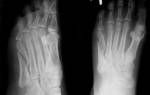

Боль под пальцами на ноге описывается как жгучая, ноющая. Она зависит от степени и разновидности артроза ступни. Кроме анализа анамнеза, диагностировать заболевание помогают лабораторные исследования (для определения воспаления), оценка размеров стопы, рентгенография. Визуализировать состояние хрящей, костей, мышц можно при помощи МРТ или КТ.

Врач оценивает появление симптомов со слов пациента, направляет его на рентгенографию, проводит измерение и оценку параметров стопы, использует методы плантографии и подографии. Степень плоскостопия устанавливается по результатам электромиографии.

Диагностировать остеопороз можно остеоденситометрии и рентгенографии костей стопы. При лечении требуется корректировать состояние, вызванное основным заболеванием, остановить или замедлить изменения в костной ткани, снять проявления боли в тканях конечности и в стопе под пальцами.

Требуется пройти рентгенографию.